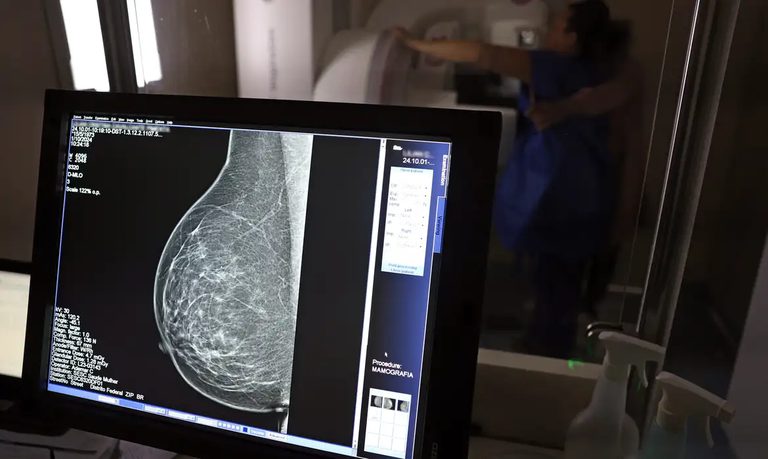

Governo do Brasil amplia o cuidado oncológico no país (Fotos: JOSÉ CRUZ/AGÊNCIA BRASIL)

Programa Agora Tem Especialistas amplia prevenção e tratamento oncológico no SUS: 781 mil casos projetados pelo INCA até 2028, mamografias para 40-74 anos, recorde em quimioterapia e vacina HPV a 85%. Avanços reais para diagnóstico precoce e equidade. Fonte: Ministério da Saúde e INCA.

Mamografia gratuita para mais mulheres

Agora, mulheres de 40 a 49 anos – mesmo sem sintomas – podem fazer mamografia no SUS, além de 50 a 74 anos. Em 2025, foram 3 milhões de exames bilaterais, e a Pesquisa Vigitel/MS 2025 mostra que 92% das mulheres de 50-69 anos já realizaram o teste. Isso eleva as chances de cura em até 90% nos estágios iniciais.